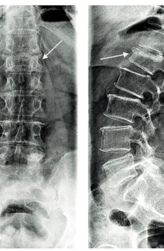

Компрессионный перелом позвоночника